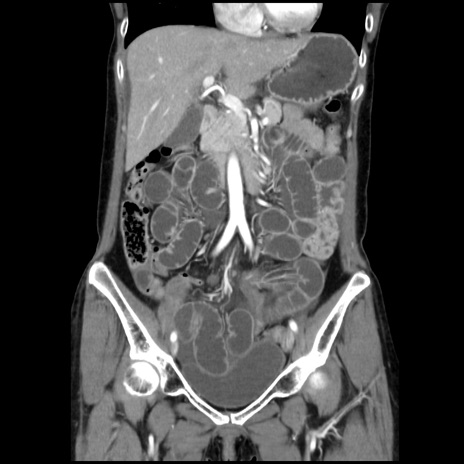

症例32(冠状断像)

【症例】40歳代 女性

【主訴】上腹部痛、嘔気・嘔吐

【現病歴】約9時間前頃から急に上腹部痛、嘔気、嘔吐が出現。改善しないため救急要請。

【既往歴】子宮頚癌(広汎子宮全摘術、放射線療法)、腸閉塞

【身体所見】腹部:平坦、軟、腸雑音亢進、上腹部を中心に腹部全体に圧痛あり。

【データ】WBC 8400、CRP 0.03